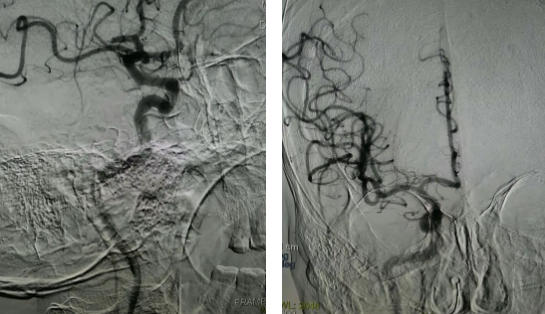

取栓前/取栓后

手术团队精准定位患者右侧大脑中动脉M2段栓塞,通过取栓支架及负压抽吸成功取栓,恢复血管通畅,患者生命体征平稳,无手术并发症,安返病房。